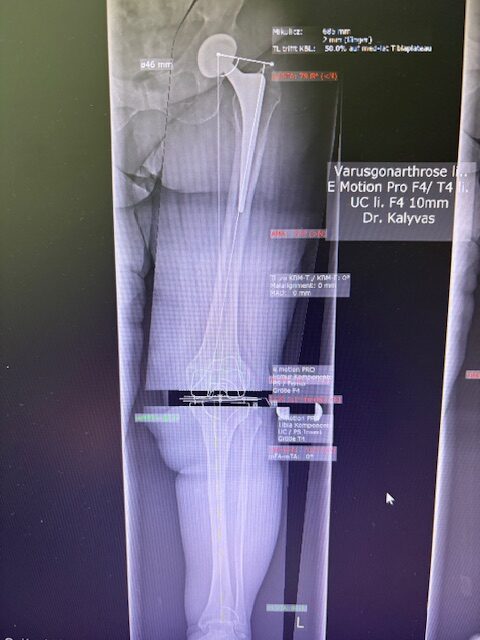

Ο προεγχειρητικός ψηφιακός σχεδιασμός

Πραγματοποιήθηκε σε ειδική ακτινογραφία ολόκληρων των δύο κάτω άκρων. Σε αυτό το ψηφιακό μοντέλο σχεδιάστηκε με ακρίβεια το είδος, το μέγεθος και η ακριβής θέση των προθέσεων, με βάση τα ανατομικά χαρακτηριστικά της ασθενούς.

Ο ψηφιακός σχεδιασμός επιτρέπει απόλυτη εφαρμογή των μοσχευμάτων, ελαχιστοποιώντας τα περιθώρια απόκλισης και εξασφαλίζοντας άριστη ευθυγράμμιση και κινηματική ισορροπία του γόνατος.

Τα εμφυτεύματα που χρησιμοποιήθηκαν στο γόνατο της ασθενούς είναι της Aesculap: E-Motion Pro, μηριαίο μέγεθος 4, κνημιαίο μέγεθος 4, με ενθέμα (inlay) 10mm.